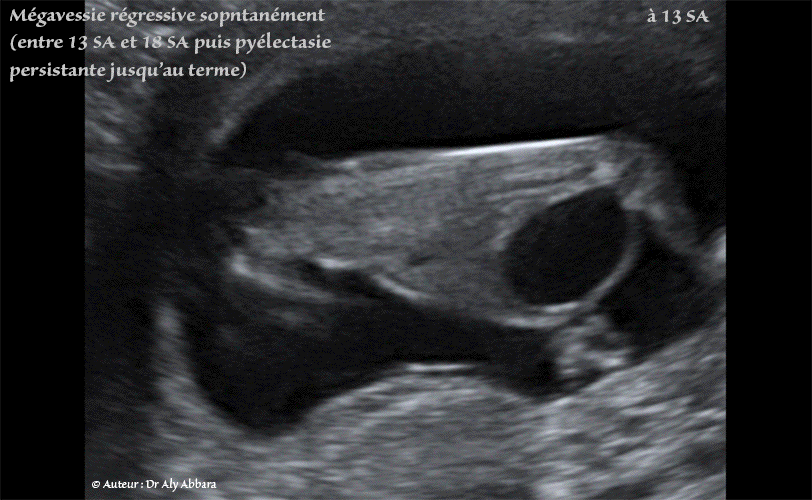

Mégavessie régressive spontanément entre 13 et 18 SA - Pyélectasie rénale bilatérale progressive - Foetus du sexe masculin

Auto diaporama (format GIF) d'images échographiques animées montrant une mégavessie chez un fœtus de 13 SA, du sexe masculin ; cette pathologie vésicale était associée à une discrète dilatation de la partie proximale de l'urètre postérieur (signe du trou de la serrure) et à une pyélectasie rénale bilatérale minime.

L'évolution ultérieure à 18 SA, puis à 23 SA montre la normalisation spontanée du volume de la vessie, avec par contre, on note la progression de la pyélectasie bilatérale au fur et à mesure de l'avancement de l'âge de la grossesse : bassinets rénaux à 4 et 4,2 mm à 18 SA et 7 et 8,6 mm à 23 SA…